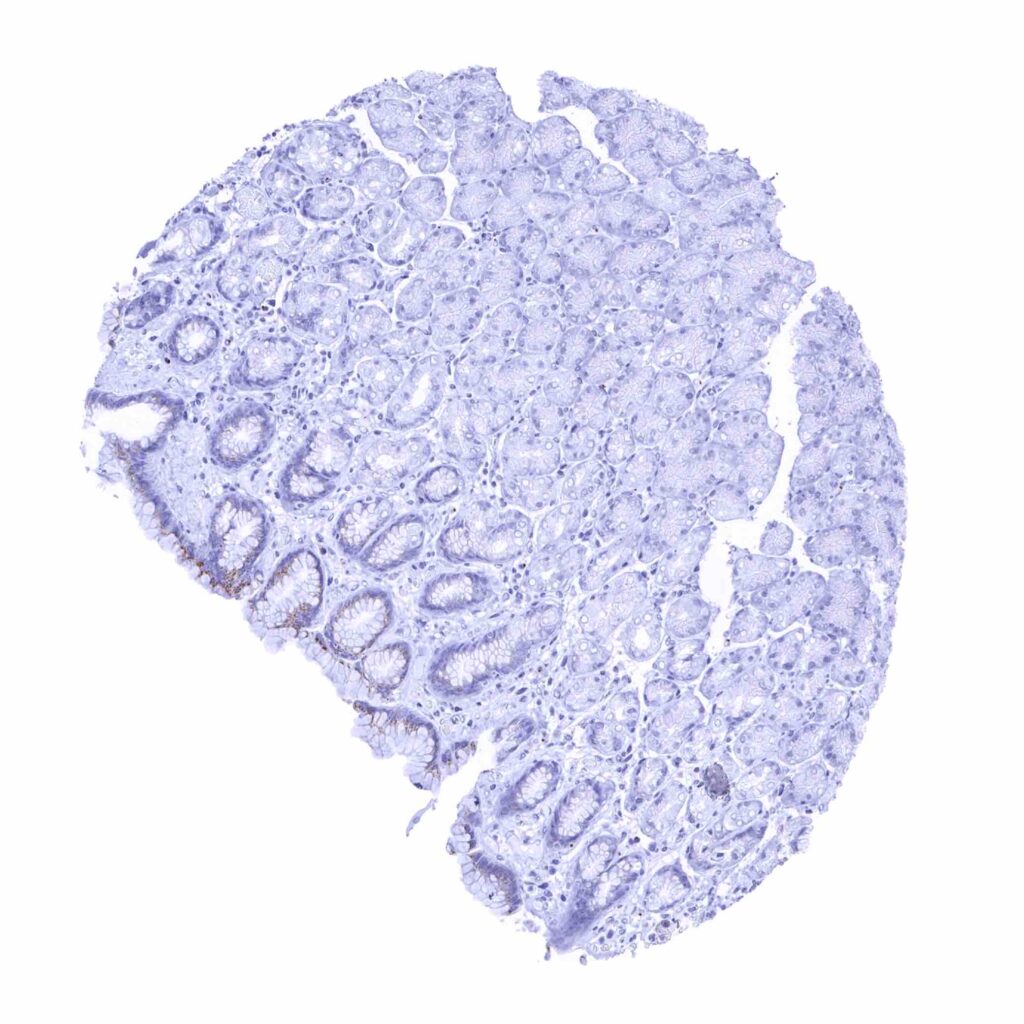

Appendix, mucosa – Prostein staining is lacking